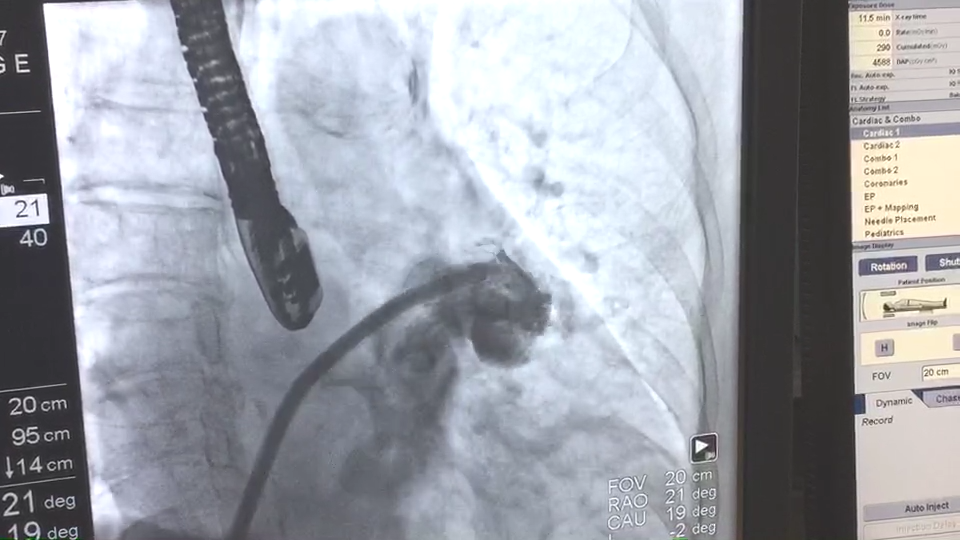

患者左心耳造影图

当日接受手术的患者为一名74岁女性,伴有高血压,脑卒中,心律失常。入院评估CHA2DS2-VASc 评分为3分,HAS-BLED评分为4分。术中造影测量左心耳大小,锚定区测量结果为19.6±2.8mm,开口部区域测量结果为22.0±2.2mm。陶凌教授与其团队讨论后,决定选用彩神在线网信彩票-彩神通免费版下载-彩神8争霸vlll-彩神购彩购彩大厅-彩神软件陆立根免费版-彩神ll争霸3-彩神ll彩神8-彩神ll争霸彩票-拼搏在线彩神网网页版科技自主研发的LAmbre™左心耳封堵器系统2430型号的封堵器进行手术封堵。术后经造影对比及超声结果显示手术封堵效果出色,患者左心耳封堵完全,无残余分流。陶凌教授对此次LAmbre™左心耳封堵器的植入结果表示满意。陶凌教授认为LAmbre™左心耳封堵器系统在术中可轻松实现回收和再释放,便于调整最佳封堵位置,且操作可控,让左心耳封堵手术更安全、简单、有效。